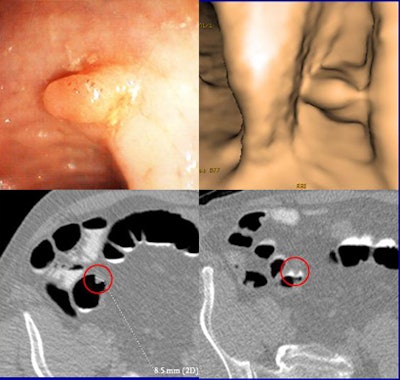

| VC and colonoscopy both detected an 8.5-mm sessile lesion that was removed at colonoscopy and proved to be an adenocarcinoma. The 58-year-old male patient had a family history of colorectal cancer. Clockwise from upper left are endoscopy image, 3D VC, and 2D axial views (bottom). All images courtesy of Dr. Daniele Regge. |

Virtual colonoscopy missed two cancers larger than 1 cm, though it found all of the small ones, Regge said. Both of the cancers were visible retrospectively on the CT data, he said, so these important misses might be attributed to a lack of training.